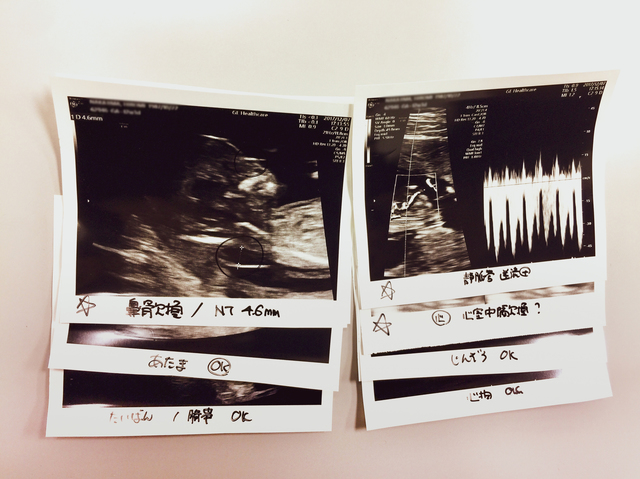

依田恵美さん(仮名・30歳の会社員)は、通常の妊婦健診の超音波検査で、

医師からいきなり「子どもに染色体異常があると厚くなるといわれている『NT』と呼ばれている部分が通常より厚い」と言われた。

妊娠11週(3ヵ月)のことだった。中期中絶のことなど何も知らないごく普通の幸せな妊婦が、いきなり、頭が真っ白になるようなことを言われたのだ。

恵美さんの赤ちゃんには心臓病をはじめ次々とダウン症の合併症が見つかった。